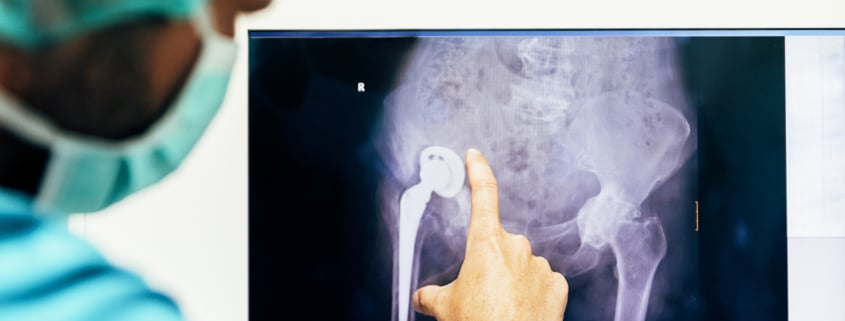

· Total hip replacement – usually performed to treat osteoarthritis of the hip that has progressed to the point of severe and constant pain that interferes with movement. The damaged part of the joint is cut away or removed, including the end of the femur (the ball of the joint) and cartilage and soft tissues from the inside of the joint. They are replaced with a smooth ball that fits into a prosthetic socket usually made of ceramic or steel.

· Hip resurfacing – similar to total hip replacement, prosthetic materials are implanted in the body to replace the hip joint. With hip resurfacing, the head of the femur is fitted with a smooth cap instead of removing the bone area and replacing it with a ball. The socket implanted in the hip fits the resurfaced femur for smooth and pain-free movement.

· Partial hip replacement – if the end of the femur suffers a bad fracture, a partial hip replacement may be necessary to restore movement. In that case, the femur head is removed and replaced with a ball but the rest of the hip joint is left intact.